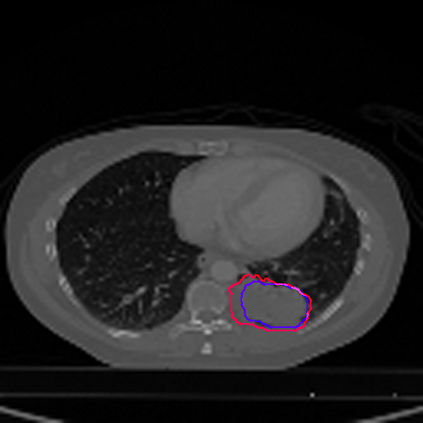

Lung cancer is a leading cause of death in most countries of the world. Since prompt diagnosis of tumors can allow oncologists to discern their nature, type and the mode of treatment, tumor detection and segmentation from CT Scan images is a crucial field of study worldwide. This paper approaches lung tumor segmentation by applying two-dimensional discrete wavelet transform (DWT) on the LOTUS dataset for more meticulous texture analysis whilst integrating information from neighboring CT slices before feeding them to a Deeply Supervised MultiResUNet model. Variations in learning rates, decay and optimization algorithms while training the network have led to different dice co-efficients, the detailed statistics of which have been included in this paper. We also discuss the challenges in this dataset and how we opted to overcome them. In essence, this study aims to maximize the success rate of predicting tumor regions from two dimensional CT Scan slices by experimenting with a number of adequate networks, resulting in a dice co-efficient of 0.8472.